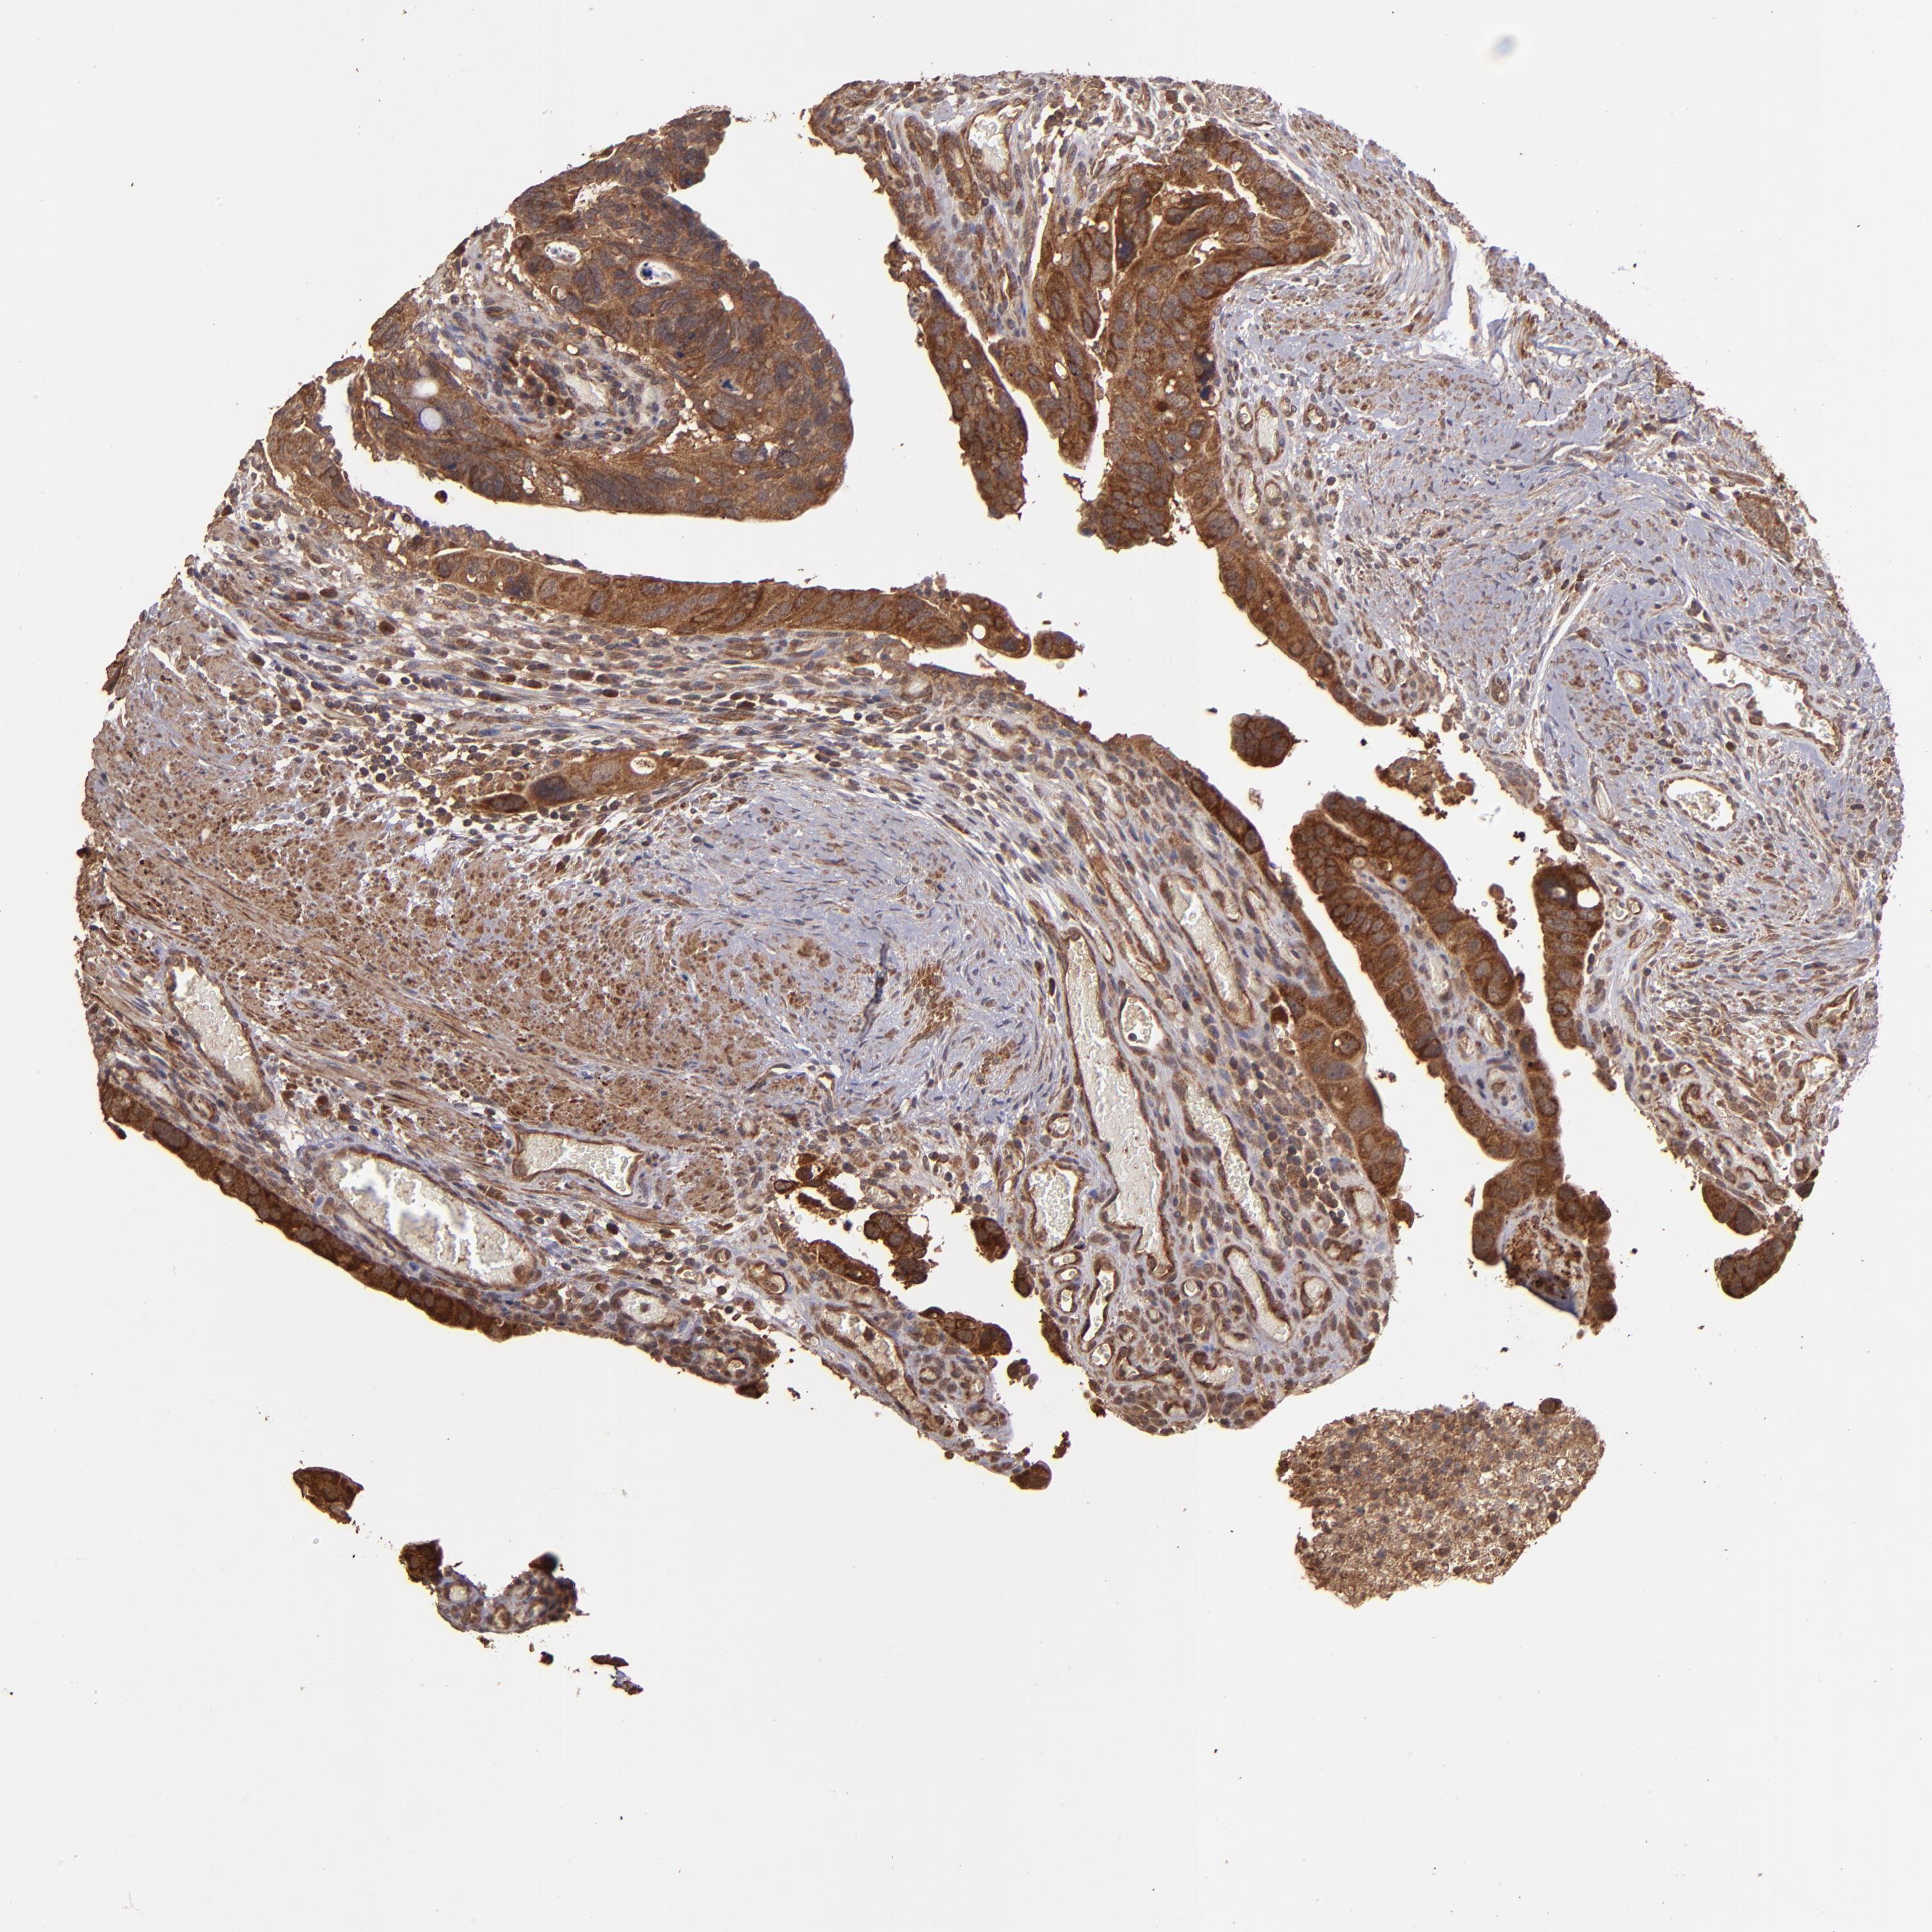

CANCER COLORECTAL CANCER Show tissue menu

Colorectal cancer

Human cancer

Colon adenocarcinoma